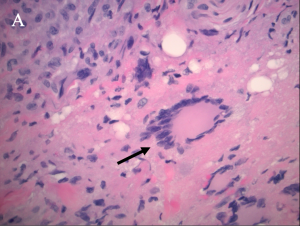

There are four subtypes of adult xanthogranulomatous disorders and one juvenile xanthogranuloma. Xanthogranulomatous disorders are non-Langerhans histiocytoses. Like xanthomas, the lesions in these disorders contain foam cells; they differ from xanthomas in the presence of Touton giant cells, a type of multinucleated giant cell with a high lipid content, and varying degrees of fibrosis and necrosis (Images 3A, 3B).

Xanthogranulomas differ from xanthomas by the presence of Touton giant cells, a type of multinucleated giant cells with high lipid content, and areas of necrosis (Images 3A, 3B, 4A, 4B).